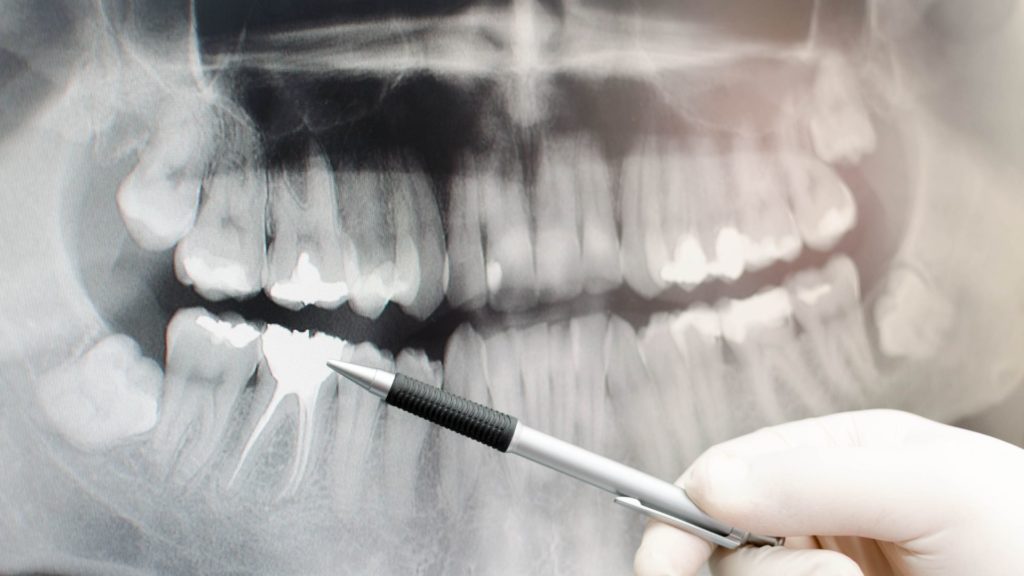

Imagen Dental Intraoral. La tecnología en el campo odontológico ha ido evolucionando a lo largo del tiempo ayudando tanto al odontólogo como a los pacientes a obtener mejores diagnósticos en menor tiempo y a mayor alcance de todos.